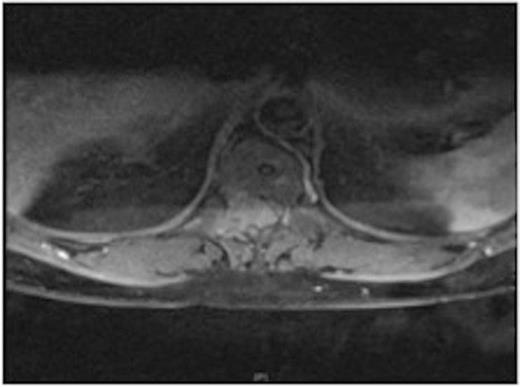

MRI showing the T10-11 extra-dural tumour with erosion of the T12 pedicle

Due to the low-grade nature of the tumour and the spinal cord compression the advantages and disadvantages of surgery versus radiotherapy were discussed with the patient who then agreed to have the tumour surgically removed.